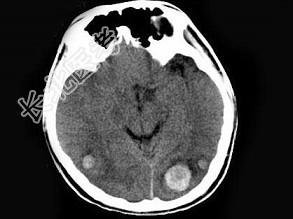

- 单项选择题男,22岁, 耳后见一直径约2cm黑痣,表现有溃烂, 近期增大明显,头痛1周, 伴咳嗽、胸闷,行头颅CT及MRI检查见颅内多发病灶, 最可能的诊断为 ( )

A、黑色素瘤脑转移